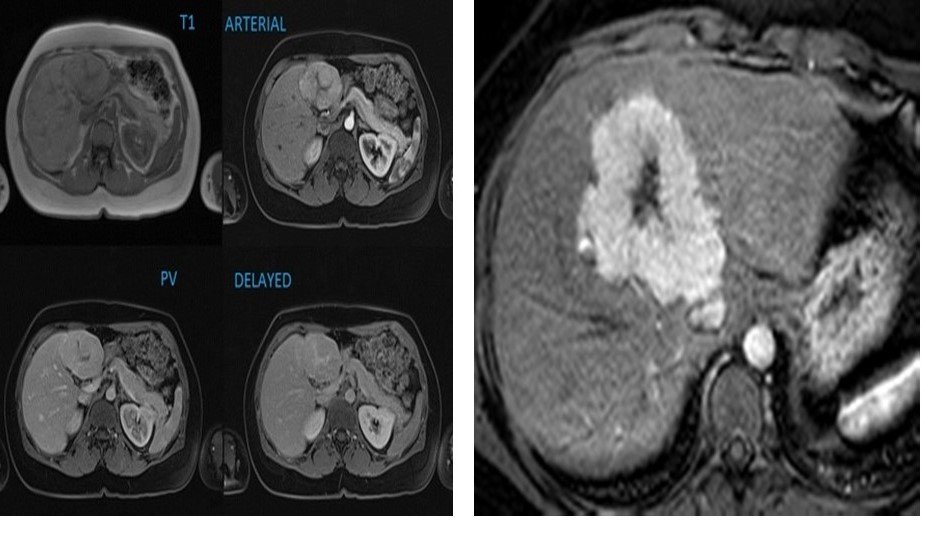

Focal Nodular Hyperplasia (FNH)

–Hyperplastic lesion, common in young females

–Intense homogeneous arterial enhancement

–Central scar characteristic

–Scar enhances on delayed phase

–MRI: T2 hyperintense scar

–No malignant potential

Summary of T1, and the various phases of the contrast study illustrating the nature of the focal liver lesion.

Note the enhancement of the central scar only on the delayed images when the rest of the lesion has washed out.

On the arterial phase, the lesion demonstrates intense homogenous enhancement, except for the central scar.